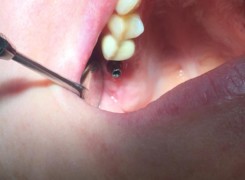

Pan Kamil zgłosił się do gabinetu po wypadku rowerowym w wyniku którego wybił ząb – lewą górną jedynkę. W takiej sytuacji została podjęta decyzja o implantacji natychmiastowej oraz zapatrzeniu pacjenta na czas integracji wszczepu w uzupełnienie tymczasowe.

Poniżej przebieg odbudowy protetycznej.